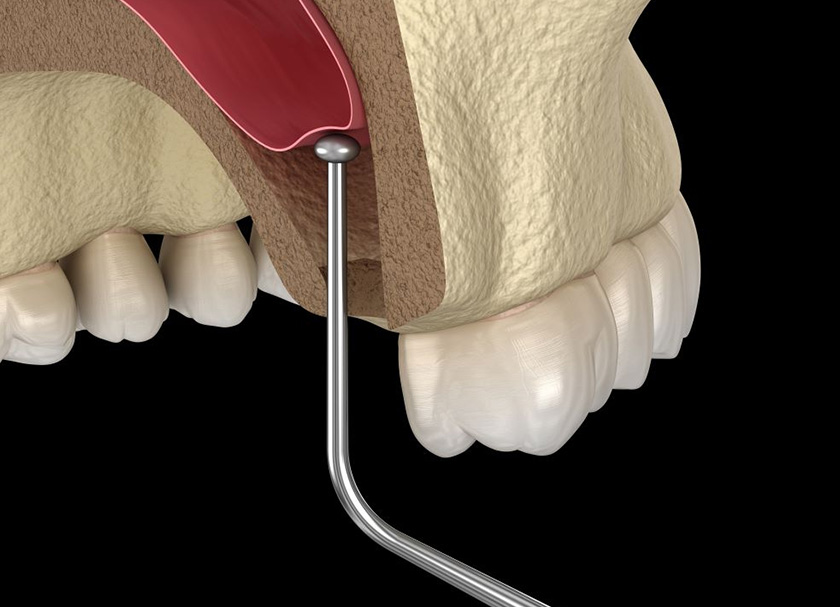

The maxillary sinus is augmented or raised during a sinus lift.

The rear of the maxilla, or upper jaw, has a series of air-filled chambers called the maxillary sinuses. A dentist can install an implant with additional bone by elevating the sinus and transplanting bone.

- The surgeon will locate the rear of your gum tissue and make incisions to reveal the bone.

- To prevent damaging the sinus membranes, your surgeon will only remove a small portion of the bone.

- Your doctor will raise the membrane by bringing the sliced bone fragment into the sinus cavity.